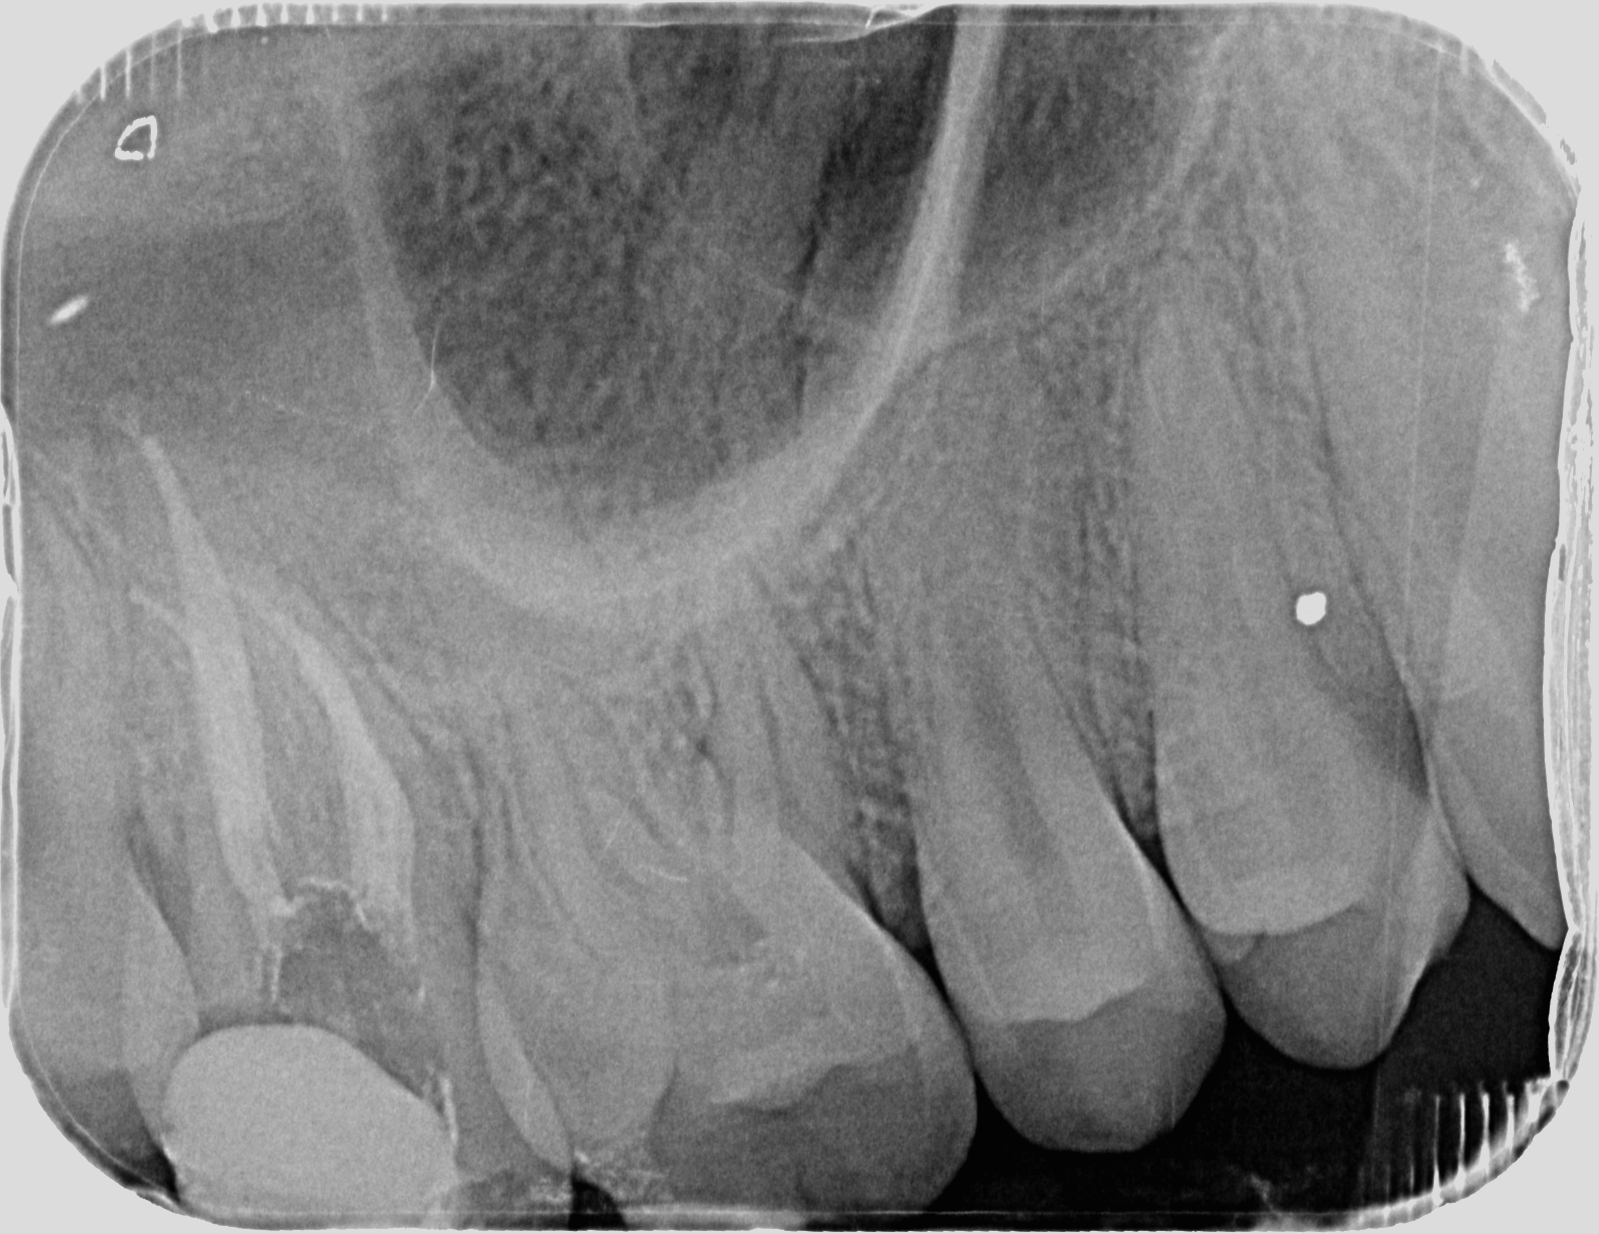

Acude a la clínica del máster un chico de

17 años de edad, sin antecedentes médicos ni odontológicos de interés, remitido

de la policlínica de la universidad europea ya que limpiando una caries

profunda llegaron a la pulpa. Presentaba en ese momento vitalidad aumentada,

palpación y percusión negativas y sondaje fisiológico, por tanto se diagnosticó

de pulpitis irreversible, cuyo tratamiento es la biopulpectomía del 17.